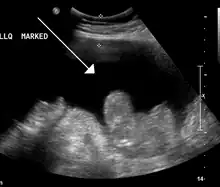

Ascites in a person with abdominal cancer as seen on ultrasound

Ultrasound investigation is often done before attempts to remove fluid from the abdomen. This may reveal the size and shape of the abdominal organs, and Doppler studies may show the direction of flow in the portal vein, as well as detecting Budd–Chiari syndrome (thrombosis of the hepatic vein) and portal vein thrombosis. The sonographer also can estimate the amount of ascitic fluid, and difficult-to-drain ascites may be drained under ultrasound guidance. An abdominal CT scan is more accurate than a sonogram to reveal abdominal organ structure and morphology.[12]